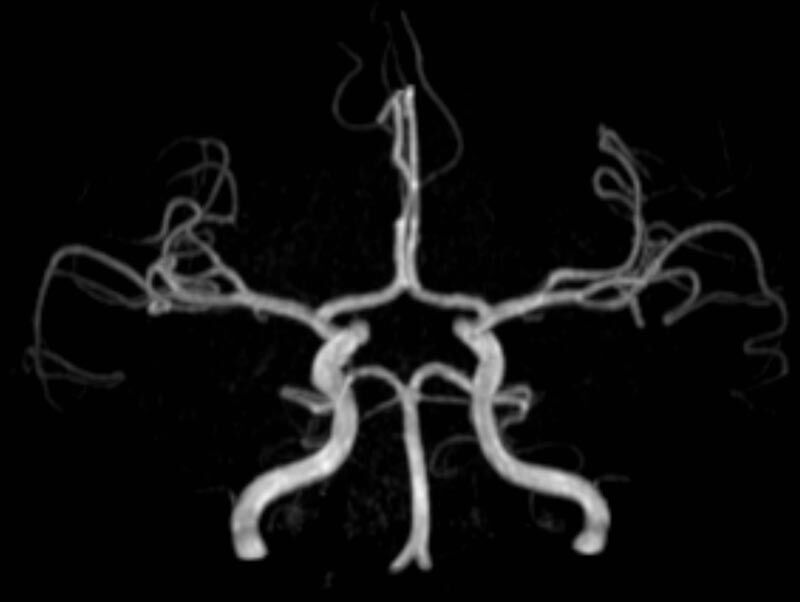

MR-Angiografie (MRA)

Angiographie ohne Kontrastmittel

• MR-Angiografie ohne Kontrastmittel

• Time of Flight (TOF)-Angiographie

• Phasenkontrastangiographie (PCA). Geeignet zur Quantifizierung Stenose-/Insuffizienzgrad z.B. bei Herzklappen, falls echokardiographisch die Untersuchungsbedingungen eingeschränkt sind.

Je nach Fragestellung und Körperregion Gefäßdarstellung ohne Kontrastmittel bei Kontrastmittelunverträglichkeit oder terminaler Niereninsuffizienz möglich.

Ganzkörper Angiographie mit Kontrastmittel

• MR-Angiographie mit Kontrastmittel

• Erfassung arterieller und venöser Gefäße/Bypässe aller Körperregionen mit 3D-Rekonstruktion

• je nach klinischer Fragestellung zeitaufgelöste MR-Angiographie (4D-MRA) z.B. bei Frage arteriovenöse Fistel/ Shunt oder Darstellung Unterschenkelarterien vor geplanter Bypassoperation.